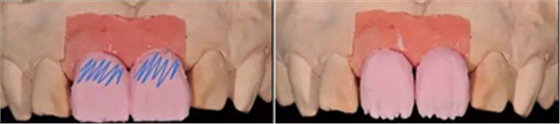

天然牙顏色分析:首先確定基礎(chǔ)顏色,A2色,觀察側(cè)切牙形態(tài)及顏色,頸部邊緣嵴有乳光效果,切緣伴有琥珀色。

將牙齒分為三部分,頸部邊緣飽和度高,切端伴有白斑

飾面瓷堆塑

牙齒形態(tài)修整

根據(jù)天然牙形態(tài)進(jìn)行牙冠形態(tài)修整、表面紋理再現(xiàn)和咬合關(guān)系調(diào)整

角度螺絲通道全瓷基臺(tái)一體冠制作完成

染色、上釉,再現(xiàn)天然牙的顏色特點(diǎn)。